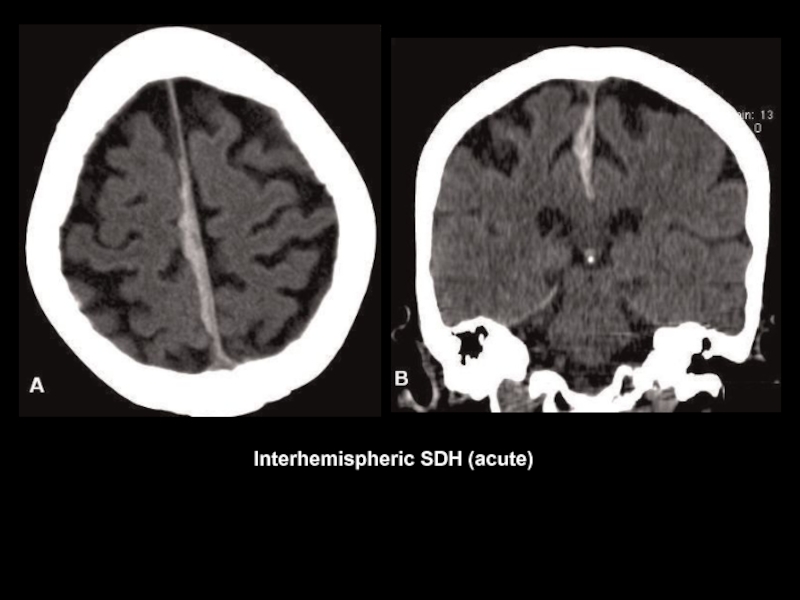

Слайд 47

Interhemispheric SDH (acute)